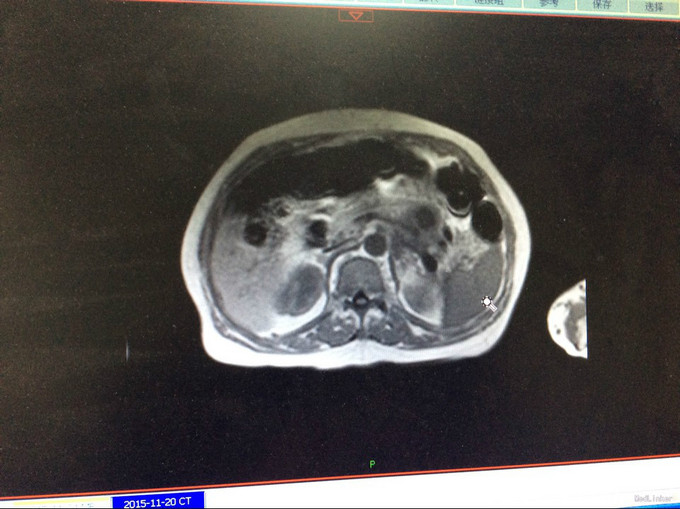

查体:生命体征平稳。神智清,查体合作,面容正常,淋巴结未触及肿大。双肺听诊呈清音,为闻及干湿罗音及哮鸣音;心率78次/分,律齐,无异常心音及心脏杂音;腹平软,肝脾肋下未及,未触及肿块,无压痛及反跳痛,肠鸣音正常。双下肢无水肿,生理反射存在,病理反射未引出。专科查体:无明显异常。辅助检查:湖北省中医院CT示:胰腺占位。CT检查示:1.结合原CT、MR检查,胰腺体尾部及周围异常改变,考虑胰腺炎伴坏死囊性变可能性大,与2015-11-20CT相比较,囊性病变略缩小;腹膜后淋巴结增多增大,大致同前;2. 所及肝脏多发囊肿;肝右叶后段其中一个病变边缘可疑强化,大小与前次相仿;3. 左侧肾上腺饱满。 MRI检查示: 胰腺体尾部及周围异常改变,考虑胰腺炎伴坏死囊性变可能性大,合并肿瘤性病变待排,病变累及腹膜伴腹膜后淋巴结增多增大,腹腔少许积液,请结合检查结果考虑;2. 所及肝脏多发囊肿;肝右叶后段其中一个病变边缘可疑强化,需鉴别于血管瘤与转移性病变,建议随访复查;3. 左侧肾上腺饱满;4. 所及右侧胸廓外小结节(层面16-7),直径约4mm,不除外右乳的病变:5. 所及腰椎骨性纵裂畸形。病理检查:(胰体尾部肿块穿刺组织)高分化腺癌,考虑为IPMN相关性浸润性癌。